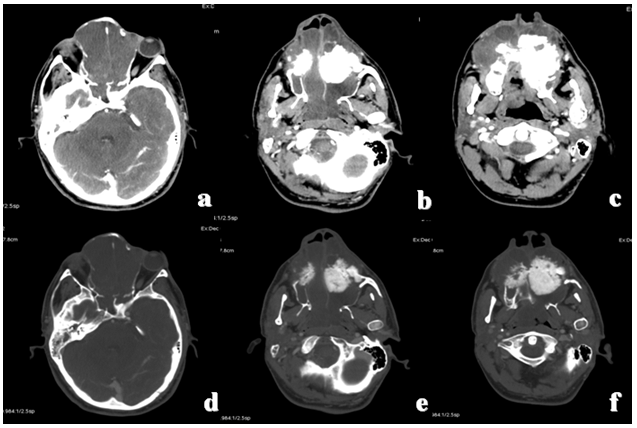

After admitting to emergency department the patient underwent contrast-enhanced computed tomography (CT) scan which revealed tumor with a major component like soft tissue, central calcification/ossification, originating in the left upper quadrant of the maxilla and invading the nasal cavity, the ethmoid cells, the sphenoidal and frontal sinuses, the right upper quadrant of the maxilla, the left alveolar process, the hard palate and the base of the orbit without involvement of the orbital adipose tissue.

Computed tomography scan examination before and after injection of contrast medium also showed the involvement of the tumor mass to the parotid gland, the masseteric fossa and the infra-temporal fossa bilaterally with multiple increased lymph nodes on mandibular angle and in lateral cervical region the invasion (Figure 1) and (Figure 2). We elaborated three-dimensional images to better define the extension of the lesion (Figure 3). In the suspicion of distal localization the patient underwent CT whole body which was negative.

Cursor on image to zoom/Click text to open image

Figure 1: Computed tomography scan after injection of contrast medium. Axial images evaluated (a-c) with soft tissue window and (d-f) with bone tissue window (d, e, f) revealed tumor with a major component like soft tissues, central calcification/ossification, originating in the left upper quadrant of the maxilla and invading nasal cavity, ethmoid cells, sphenoidal and frontal sinuses, the right upper quadrant of the maxilla, left alveolar process, hard palate and the base of the orbit without involvement of the orbital adipose tissue.